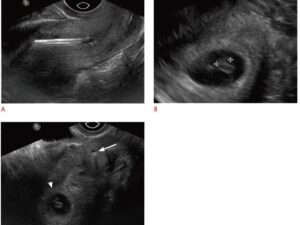

An ultrasound revealed something unexpected. The doctor’s face shifted, his eyes locking on mine. Then he said a single word that made my stomach drop: “Emergency.” 😳

The ultrasound brought clarity. The doctor smiled with reassurance and said, “We can help her with a small procedure today.” 😌⚡ What we thought were minor backaches were signals of something that could now be corrected easily. A small kidney stone had traveled and caused her discomfort 🪨.